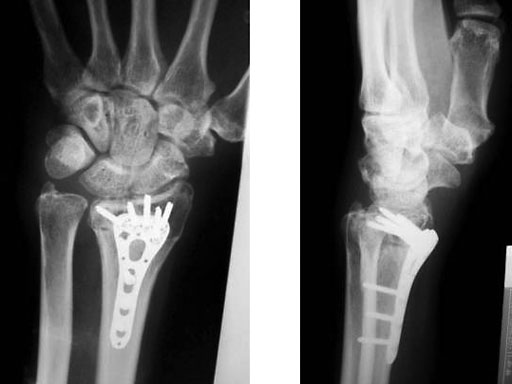

Age 63, male, motorcycle accident

Fig 1a-b Preoperative x-rays

Fig 2a-b Post-op immediate